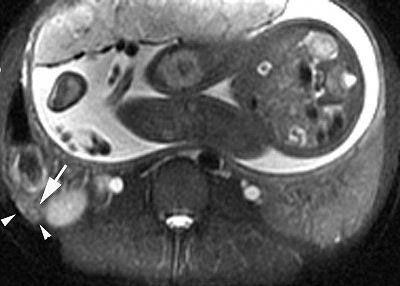

| Same patients as above. Axial fat-saturated SSFSE confirms the presence of periappendiceal edema as a rim of high SI (arrowheads) around the fluid-filled distended appendix (arrow). Surgery and pathology confirmed the diagnosis of uncomplicated acute appendicitis. Image courtesy of Dr. Ivan Pedrosa. |